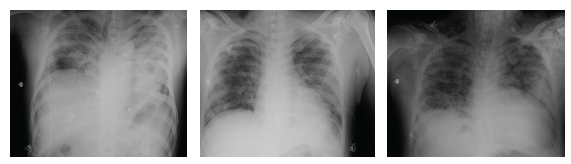

On November 28, 2020, the patient presented anxiety and increased dyspnea. Laboratory tests showed leukocytosis with neutrophilia and increased bilateral infiltrates in both lung fields in the chest X-ray, evolved with progressive deterioration of general condition with severe hypoxemia in the context of Acute Respiratory Distress Syndrome (ARDS) that required orotracheal intubation, connection to mechanical ventilation with requirements of high Fio2, and management of airway pressures. Progression to multi-systemic organ failure with need for vasopressor support. During the 10 days in which the patient remained intubated, he received psychological support, and a family member (who received psychological support throughout the patient's stay in the unit) was allowed daily admission. The hospital authorized psychological and family support during the patient's stay in the COVID intensive care unit. On leaving the ICU, the patient mentioned that, under sedation, he felt the support of his therapist: in the reverie produced by the effect of the sedatives, he visualized her sitting next to him, accompanying him, and sending him rays of light, and he commented that he felt very calm at that moment. He would ask her: "How long will I be here? How are we doing?" And he received an answer from the therapist, not in words, but mentally: "calm down, it won't be long, everything will be all right". He affirms that he saw her smiling and assured of what she was saying, and he felt very calm. He also commented that he heard, on several occasions, the doctors and nurses talking to each other, and he was very anxious when he knew from what he heard that things were not going well. The patient and his family received daily psychological therapy support during his stay in the hospital.